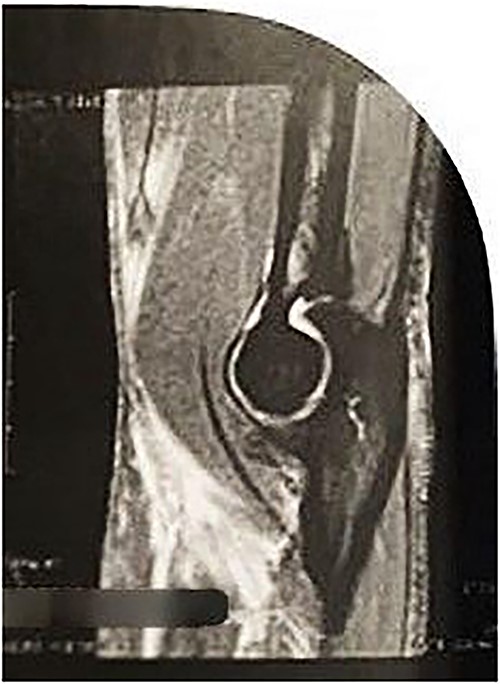

On physical examination (Fig. 1), the patient exhibited a visible deformity of the arm (inverted Popeye sign), a positive Hook test for distal biceps injury, symmetric elbow flexion strength, slightly decreased supination strength with pain, but with a complete range of motion for passive and active pronation-supination and flexion-extension. Ultrasonography and magnetic resonance imaging revealed a complete rupture of the distal biceps tendon (Figs 2–4).

Axial MRI image showing absence of the biceps tendon in the region of the radial tuberosity and edema in the area.